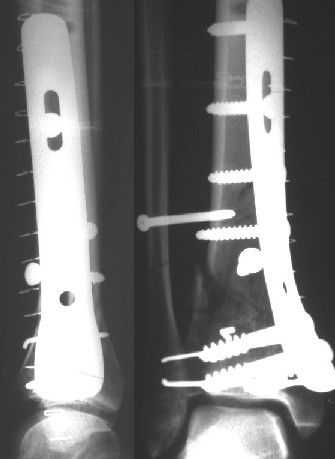

Операции: 1 Клиновидная резекция на вершине деформации м\берцовой кости.

2 Тугоподвижный ложный сустав н\3 б\берцовой кости. Рубцы выполняющие пространство между отломками, канал проксимального отломка иссечены.

Одномоментное устранение деформации, остеосинтез Г-образной пластиной.

Пластика по Хахутову.

Заживление проксимальной части раны вторичным натяжением без нагноения. Рана зажила. Спицы удалены через 1,5 недели после операции.

Особого смысла в них не было.

Учитывая фон (интеллект, etc) гипсовая повязка.

На данный момент ходит при помощи костыля (без присмотра -без костыля :), разрабатывает движения в г\стопном суставе.